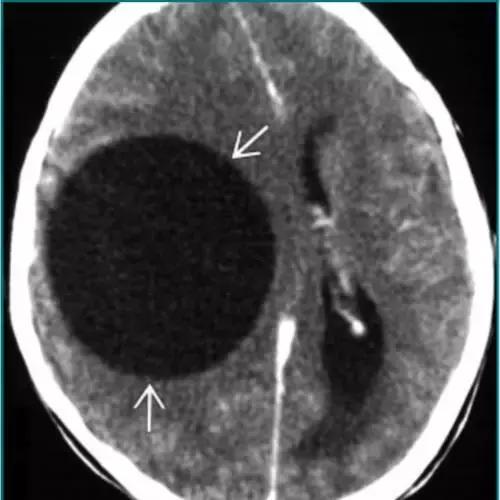

脑包虫囊肿